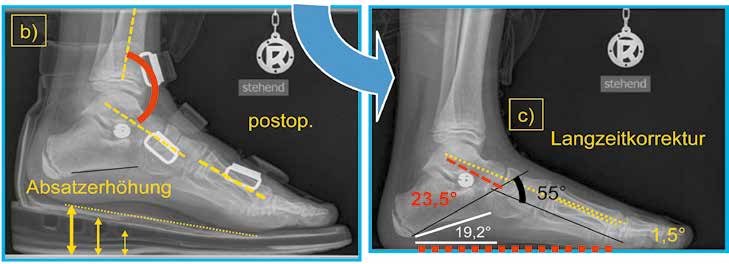

Zuletzt soll noch auf ein Korrekturphänomen hingewiesen werden, welches das postoperative Vorgehen beeinflusst: Durch die Neupositionierung des Calcaneus aus der Valgusfehlstellung in die orthograde Einstellung kommt es zu einer Zunahme der Bauhöhe zwischen dem oberen Sprunggelenk und der plantaren Calcaneusfläche (Abb. 2a u. b). Klinisch relevant wird der sich einstellende Spitzfuß; eine zusätzliche operative Intervention wurde bisher nicht notwendig – allerdings ist dies im Rahmen der Nachbehandlung zu berücksichtigen.

Die Mobilisierung der Patienten ist bereits ab dem 1. postoperativen Tag unter schmerzorientierter Vollbelastung möglich. Dem Vorliegen einer postoperativen Spitzfußeinstellung muss durch eine temporäre Absatzerhöhung begegnet werden (Abb. 3). Dies führte neben einer rascheren Mobilisierbarkeit auch zu einer Reduktion der notwendigen analgetischen Therapie.

An einem plakativen Korrekturbeispiel (männlicher Patient, Operation im Alter von 10 Jahren) werden die Achsen- und Winkelverhältnisse in der Sagittal- und Horizontalebene vor und nach der Arthrorise gezeigt bzw. unter Anwendung gängiger Mess-Verfahren dokumentiert.

Der Talokalkanearwinkel nach Costa-Bartani zeigt eine sehr gute Korrektur des Fußes in der Sagittalebene mit einem Korrekturausmaß von 23° (präoperativ 32° – postoperativ 55°) (Abb. 1a u. c).

Der Tarsometatarsalwinkel I nach Hamel verdeutlicht die Aufrichtung des Talus und damit die funktionelle Ausrichtung auf das Metatarsale I. In dem gezeigten Beispiel kommt es zu einer Korrektur von annähernd 40° (präoperativ 39,6° – postoperativ 1,5°) (Abb. 1a u. c).

Der Talus-Neigungswinkel beschreibt die Korrektur des Talus obliquus und zeigt 24° Aufrichtung des Talus im Verhältnis zur Bodenfläche (präoperativ 47,8° – postoperativ 23,5°) (Abb. 1a u. c).

Im Unterschied dazu wird die Einstellung des Calcaneus in der Sagittalebene im gezeigten Fall nicht beeinflusst (präoperativ 18,9° – postoperativ 19,2°) (Abb. 1a u. c).

Die Betrachtung der Ergebnisse zeigt eine suffiziente Ausrichtung des Talus zum Metatarsale I in der Sagittalebene wie in der dorsoplantaren Darstellung. Diese Korrektur der knöchernen Strukturen bleibt nicht ohne Auswirkung auf die Längenverhältnisse der Sehnen mit dem beschriebenen konsekutiven Spitzfuß und der damit empfohlenen temporären Absatzerhöhung (Abb. 1b).